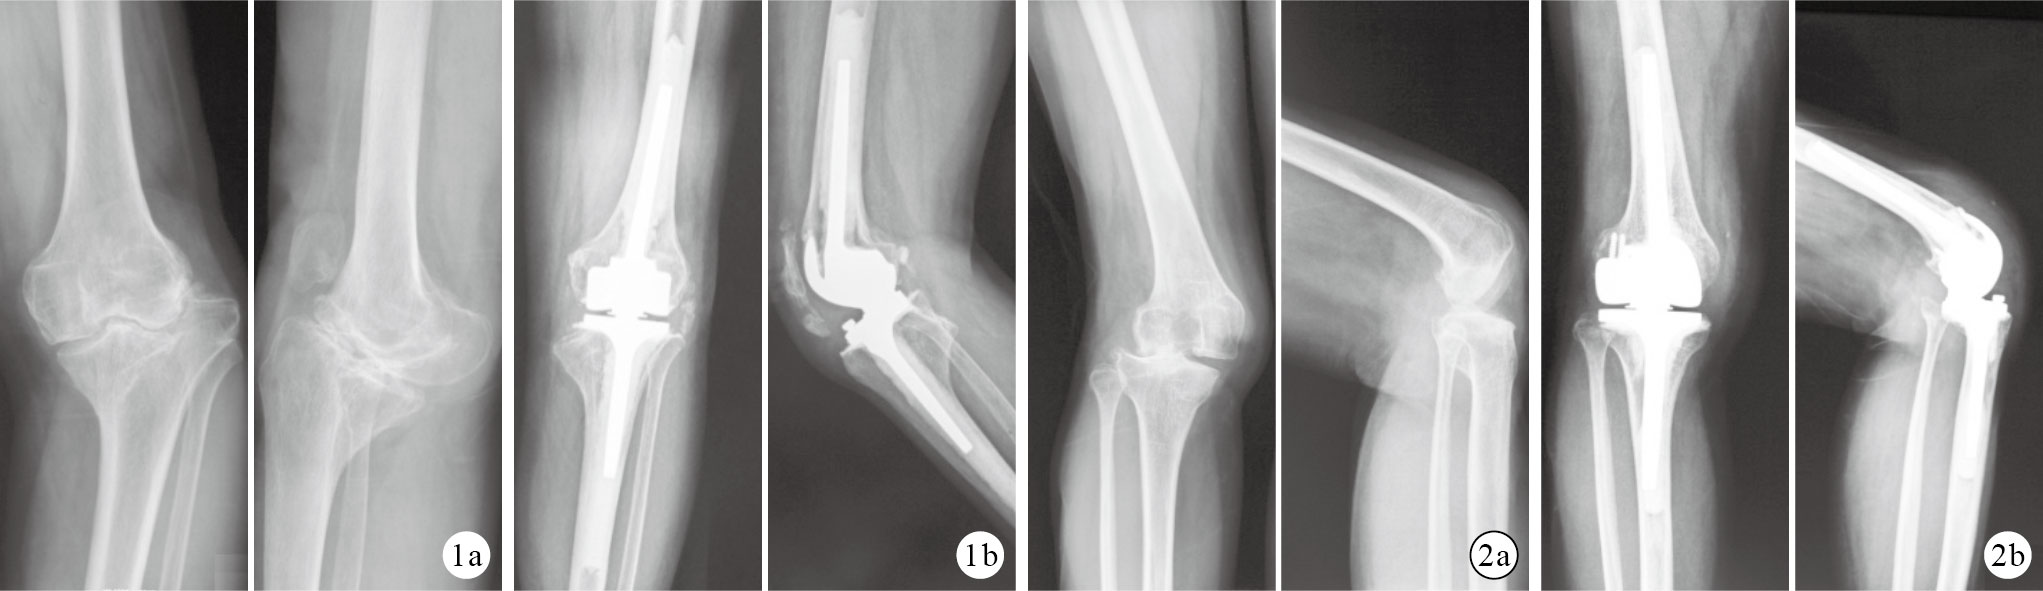

本組手術時間70~90 min,平均78 min;手術開始至拔出引流管期間出血量400~1 000 mL,平均650 mL;住院時間14~18 d,平均15.2 d。術中均無神經、血管損傷。1例(4.17%)術中發生髕骨橫形撕脫性骨折,給予愛惜康不可吸收縫線固定,術后角度可調式支具外固定3個月后骨折愈合。術后1例(4.17%)切口出現滲液、紅腫,經換藥后愈合;其余患者切口均Ⅰ期愈合。24例均獲隨訪,隨訪時間2~10年,平均5.5年。2例(8.33%;創傷性關節炎及夏科關節病各1例)分別于術后3個月及1年出現假體周圍感染,給予取出假體,抗生素骨水泥曠置,二期采用旋轉型鉸鏈膝關節假體行翻修術。術后3例(12.50%)出現膝前痛,予以塞來昔布止痛治療,術后3個月疼痛逐漸緩解;4 例(16.67%)出現10°伸膝遲滯,囑患者床旁加強患膝主動及被動屈伸功能鍛煉,術后半年無明顯伸膝遲滯。X線片復查示假體周圍未見明顯透亮帶、骨溶解,假體無明顯下沉,下肢力線無明顯改變。見圖 1。本組3例夏科關節病隨訪時間分別為2、3.5、4年,X線片示未見明顯松動征象。

圖1

患者,女,64歲,左膝創傷性關節炎正側位X線片 ? 術前 ? 術后2年 ? ?術后1年及末次隨訪時膝關節KSS評分、VAS評分及髖關節屈伸活動度均顯著優于術前,差異有統計學意義(P< 0.05);末次隨訪與術后1年比較差異均無統計學意義(P> 0.05)。見表 1。末次隨訪時,KSS臨床評分獲優5例、良8例、中10例、差1例,優良率為54.2%;KSS功能評分獲優1例、良4例、中9例、差10例,優良率為20.8%。末次隨訪時,SF-36量表評分中除生理功能及軀體疼痛評分顯著低于四川省年齡> 60歲城市男性參考值(t=2.42,P=0.02;t=5.26,P=0.00)外,其余各項評分與參考值比較差異均無統計學意義(P> 0.05)。見表 2。